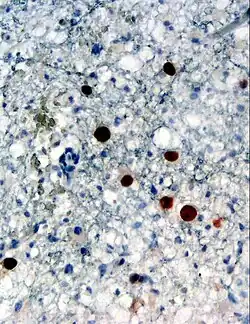

| Immunohistochemical detection of Human polyomavirus 2 protein (stained brown) in a brain biopsy (glia demonstrating progressive multifocal leukoencephalopathy) | |